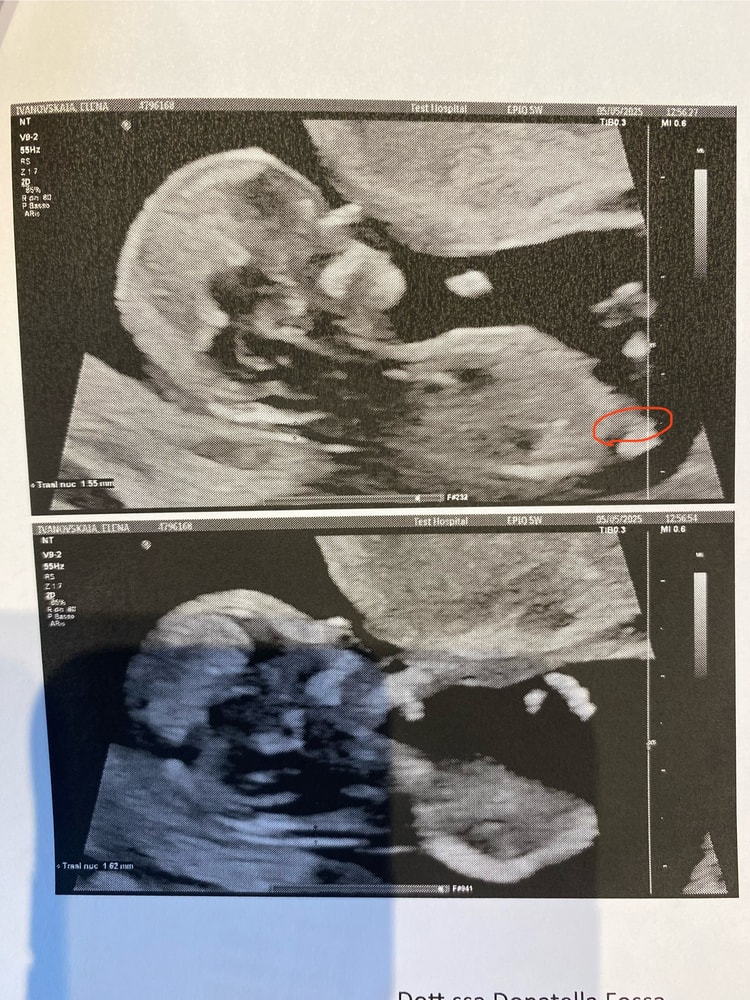

Светлана, вот красным отметила, где возможно есть какие-то намеки, но все равно не уверена он ли это?

Елена Ивановская, на первом не оно, на втором очень похоже на девочку, но фото не очень информативное, конечно